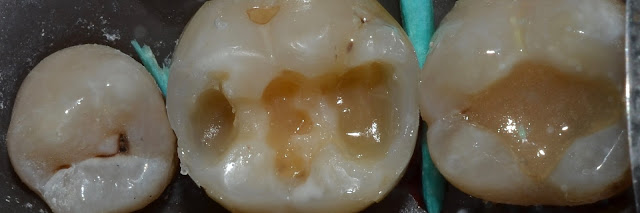

Каплан Опубликовано 26 марта, 2017 Автор Поделиться Опубликовано 26 марта, 2017 мезиально матрица мягко не айс....Не айс, там камень оставался. Я думал мягкий налет и слижется матрицей. Не слищало. Переставили конечно же. Фотку оставил, потому что просто показывает тем, кто без увеличения работает, на сколько оно важно. Хотя бы на фотках. Ссылка на комментарий

Паращук Роман Опубликовано 27 марта, 2017 Поделиться Опубликовано 27 марта, 2017 Не айс, там камень оставался. Я думал мягкий налет и слижется матрицей.Не слищало.Переставили конечно же.Фотку оставил, потому что просто показывает тем, кто без увеличения работает, на сколько оно важно. Хотя бы на фотках.таки да. когда без увеличения работаешь думаешь что все матрицы у тебя стоят идеально и там сухо как в Сахаре. С увеличением можно минут по сорок адаптировать видя что то тут не прижато,то там сочиться.))) Ссылка на комментарий